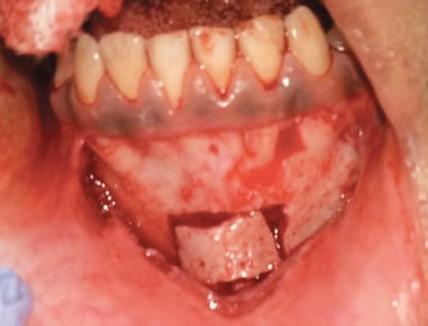

Tooth loss due to trauma often triggers residual alveolar resorption to a greater degree in the sagittal direction leading to atrophy. However, in a pediatric patient, if this defect is left untreated, it can cause further atrophy leading to collapse of the arch. In the maxillary anterior area, this is also of esthetic concern. Hence, it is viable to reconstruct the alveolar defects and restore the alveolar anatomy with superior quality of bone while the patient is still in growing phase to avoid any structural and dental malformation, as well as to provide a more novel treatment like dental implant at a later stage when growth ceases. Modes for successfully augmenting the bone are diverse. Among these, barrier membrane with guided bone regeneration, distraction osteogenesis, and bone block graft is ubiquitous. The current case report deals with the management of horizontal atrophic anterior maxillary region using autologous block bone graft harvested from mandibular symphysis, to augment the alveolar ridge and aid in esthetic and functional restoration of alveolar anatomy by restoring the defect with the bone of superior quality as well as preparing the site for receiving implant prosthesis in future when growth ceases. Bhandary M, Hegde AM, Shetty R, Augmentation of Narrow Anterior Alveolar Ridge Using Autogenous Block Onlay Graft in a Pediatric Patient: A Case Report. Int J Clin Pediatr Dent 2021;14(2):311-314.

因创伤导致的牙齿缺失通常会在矢状方向上更大程度地引发残余牙槽骨吸收,进而导致萎缩。然而,对于儿科患者,如果这种缺损不进行治疗,可能会导致进一步萎缩,进而导致牙弓塌陷。在上颌前部区域,这也涉及美观问题。因此,在患者仍处于生长阶段时,重建牙槽骨缺损并恢复具有优质骨的牙槽骨解剖结构是可行的,以避免任何结构和牙齿畸形,并在生长停止后的后期提供更新颖的治疗方法,如牙种植体。成功增加骨量(骨增量)的方式多种多样。其中,引导骨再生屏障膜、牵张成骨和骨块移植很常见。本病例报告涉及使用从下颌联合处获取的自体块状骨移植来处理上颌前部水平萎缩区域,以增加牙槽嵴,并通过用优质骨修复缺损以及为生长停止后未来接受种植修复体准备位点,来帮助牙槽骨解剖结构的美观和功能恢复。Bhandary M, Hegde AM, Shetty R, 儿科患者使用自体块状贴附移植增加狭窄前牙槽嵴:病例报告。《国际临床儿科牙科学杂志》2021年;14(2):311 - 314。